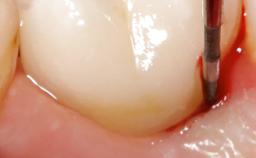

Paolo Casentini demonstrates that peri-implantitis can be successfully treated even at an advanced stage. He discusses a case in which the existing implants and prostheses were both retained while regenerating the defect and creating a band of keratinized tissue. A 69-year-old female patient was referred by her general dentist for evaluation of a recurrent infection at previously placed and restored implants in the posterior left mandible. The patient’s chief complaint was recurrent swelling and pain in the molar region of the left posterior mandible with discomfort during brushing in the same area. The patient reported receiving two implants (36 and 37) nine years earlier.